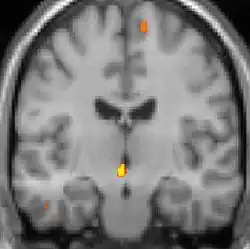

Positron emission tomography (PET) scans indicate the brain areas which are activated during attack only, compared to pain free periods. These pictures show brain areas that are active during pain in yellow/orange color (called "pain matrix"). The area in the center (in all three views) is activated only during cluster headaches. The bottom row voxel-based morphometry shows structural brain differences between individuals with and without CH; only a portion of the hypothalamus is different.[36]